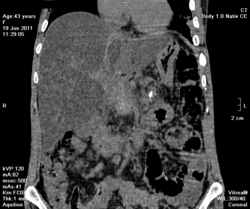

на фоне хр.калькулезного панкреатита опухоль головки поджелудочной железы, распространение на ворота печени, очень подозрительно на инвазию портальной вены и портальную гипертензию. Печень увеличена, гиподенсна, и если не ошибаюсь, цирроз.

Да, цирроз выставил, хотя конечно не такой уж он и показательный, нежели обычно с правильной атрофией и бугристыми контурами. На счет портальной вены тоже засомневался (на нативе прям как одно целое) и рекомендовал контраст, хотя, наверное, тут скорее эгоистический интерес.

Ну еще желчный пузырь и нефроптоз справа (за счет увеличенного вертикального размера печени).

По-моему в печени жировой гепатоз. А контрастирование в этом случае обязательно.

Жировой гепатоз так бы и был, если б мне не принесли сегодня кучу бамажков - данных обследований, где уже имеется диагноз цирроза. Откуда я и плясал.

Как прилежный ученик, я понимаю Вас, что основных то признаков нет - как со стороны селезенки (должного проявления портальной гипертензии), снижение плотности паренхимы печени (хотя фиброзные тяжи и тем более узлы должны бы давать повышенную плотность), отсутствие асцита! или хотя бы малого количества жидкости, отсутствие атрофических изменений и т.д...